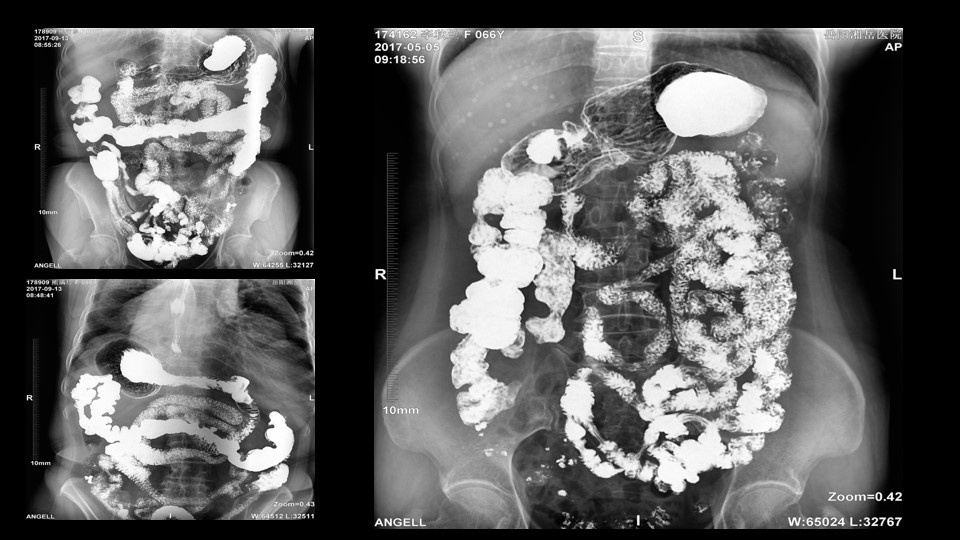

会议开始,岳阳市医学会放射分会副主委、湘岳医院放射科蔡雨主任,结合自身在放射影像的20多年经验,为参会嘉宾分享了动态DR在消化道造影中的应用价值。作为动态DR用户,蔡雨主任结合动态DR的实际拍片与操控经验,分享了动态DR技术在相关群体疾病检查上的独到优势和人文关怀。蔡雨主任说到:“随着内镜技术的发展以及CT、MR的发展,消化道造影在减少,但是这并不意味着消化道造影的价值在下降。以老年人为例,很多老年群体都患有严重的心肺疾病、或者消化道畸形,很多老年人本身就有糖尿病、高血压等等综合疾病,传统内镜的检查对于这类群体来说是一件难以忍受的痛苦,而动态DR的多项创新技术让这类群体的消化系统疾病筛查变得更为人性和精准。任何一个好的消化道造影,一定是患者、诊断医生、临床医生三方满意的结果。太阳成集团tyc122cc入口科技动态DR技术利用900万像素高清拍片、大幅面透视、高清点片、视频保存与回放等核心功能,完全满足临床对消化道气钡双重造影检查的需要。图像质量全面超越以往模拟胃肠机、影增数字胃肠机”。蔡雨主任全面演示了动态DR在食道造影、上消化道造影、小肠双对比造影、结肠气钡双对比造影中的应用,通过动态DR可以清晰获得临床诊断和评估的图像依据。

▲蔡雨主任使用动态造影图像示例